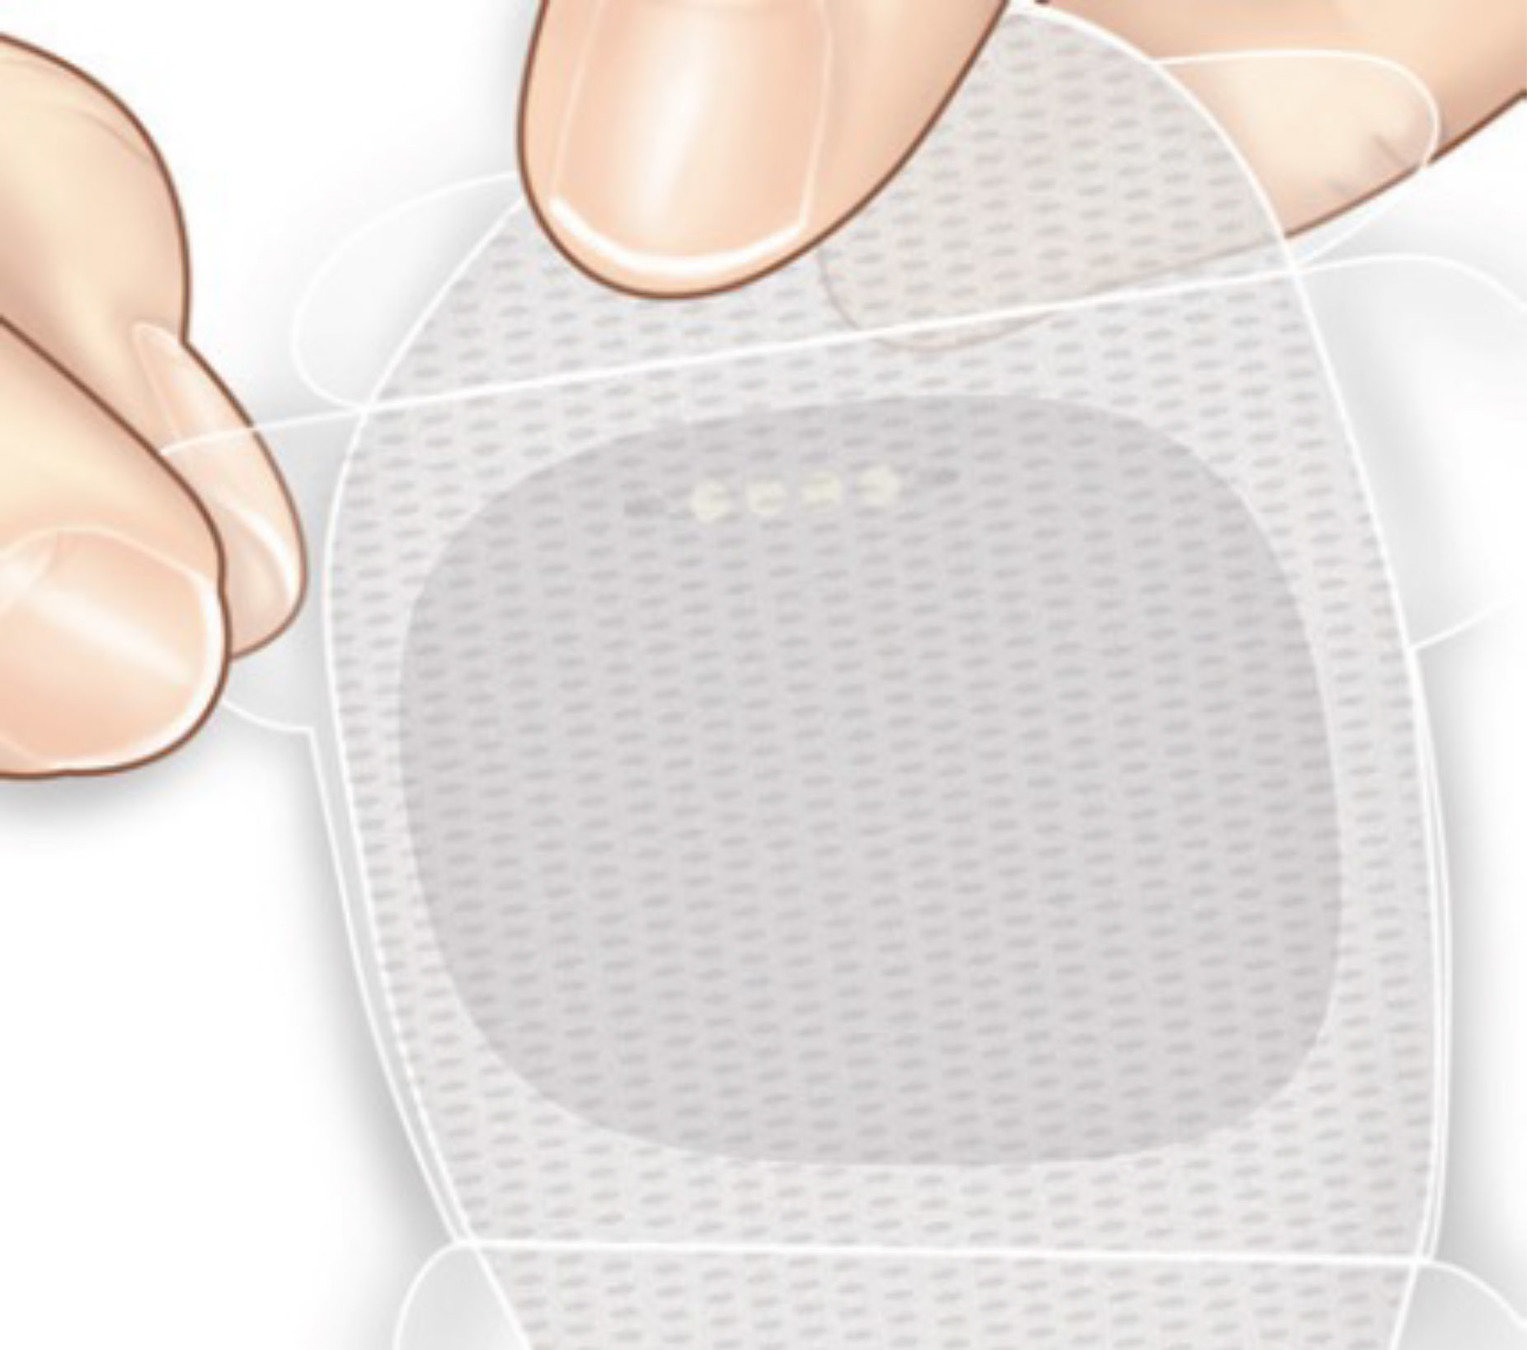

El paso 2 es colocar el transmisor inteligente sobre el parche adhesivo.

Coja un parche adhesivo y retire el papel protector con el logotipo de Eversense®.

El centro del parche es adhesivo

y es donde deberá colocar

el transmisor inteligente, tal

como se indica en la foto.

Presione el transmisor inteligente con firmeza para pegarlo al adhesivo.

A continuación, retire el trozo más grande del protector trasero transparente que queda en

el parche adhesivo.